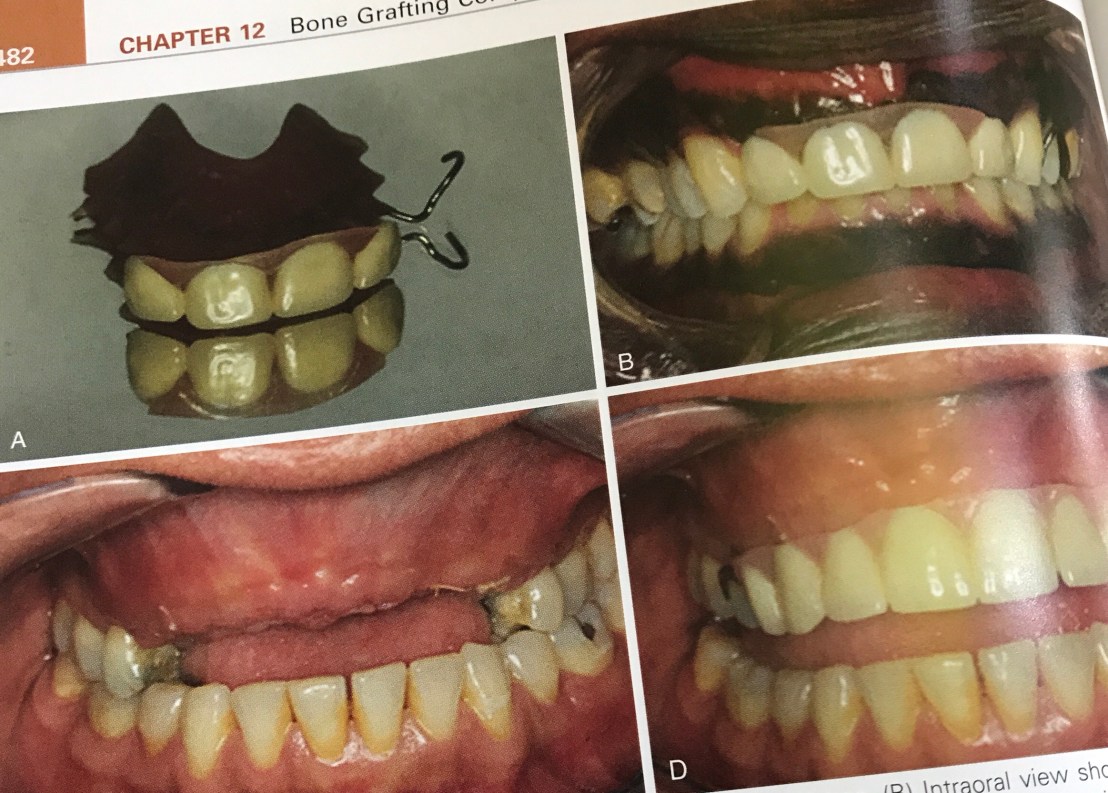

สังเกต Upper TP ชิ้นนี้ไม่มี labial flange เพื่อไม่ให้มี pressure ลงบริเวณที่ทำ Bone graft

Pressure ใดๆ ที่กดและทำให้ Block bone graft มี micro movement = 25 micron จะทำให้ Final graft volume ลดลงไป 40% ครับ

รูป D คือ Temporary Pros ที่ไม่มีแรงกดเลย สังเกตว่า เมื่อถอดออก tissue ไม่มีรอยกดตามรูปร่าง Prosthesis

รูป A แสดง screw ที่มองเห็นร่วมกับการมี Bone loss เกิดจาก Temp pros ในรูป B ที่ไม่ได้ทำการกรอ relief ให้เกิด space มากพอ

Prosthesis ในรูป C และ D คือ Essix appliance ใช้การได้ retention จากฟันเหมือน tray ฟอกสีฟัน เนื่องจากเป็น Temporary tooth support ซึ่งไม่ได้อาศัย tissue support จึงขจัดปัญหา Excessive pressure บนสัน ridge ที่ถูก augment ได้